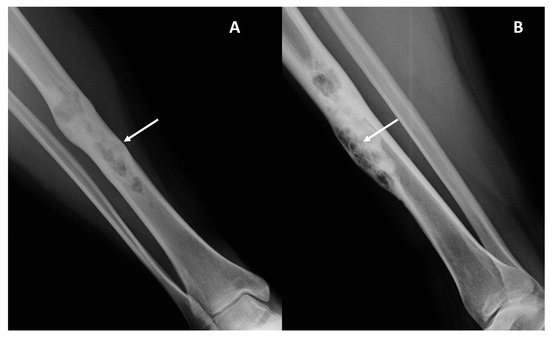

Imaging Analysis for Metastatic Risk Assessment in Adamantinoma: The Aid of Radiology in the Absence of a Histological Grading—An MRI-Based Risk Model Proposal

Background: Adamantinoma is a very rare primary malignant bone tumor. A histopathological grading is still lacking, and as a result, metastatic risk stratification at diagnosis is challenging. Due to this, imaging could play a role in prognosis prediction and treatment strategy assessment. We aimed to evaluate baseline imaging features and their correlation with the development of metastatic disease. Methods: We retrospectively collected clinical (metastatic disease) and radiological data at baseline (Conventional Radiography, CT, MRI) of all consecutive patients with a histopathological diagnosis of adamantinoma at our sarcoma center between 2006 and 2022. Tumor location, dimensions, main radiological pattern (lytic, sclerotic, mixed), Lodwick–Madewell grading, periosteal reaction, multifocality, soft-tissue extraskeletal component, peritumoral edema, peritumoral enhancement, and vascular invasion were analyzed. Associations between the above-mentioned radiological features and metastatic disease at diagnosis or during follow-up were assessed. Results: Twenty-two patients were included (15 [68.2%] women, median age 27 years old, range 7–58 years old). Six out of twenty-two patients (27.3%) developed distant metastases (only two of them were dedifferentiated adamantinoma): two patients (9%) presented with metastatic disease at diagnosis, while four patients developed metastases during follow-up (18.2%). The following radiological features represent a significant risk for metastatic disease (p = 0.01): (i) presence of an extra-skeletal component (Odds Ratio [OR] = 75.40; 95% CI = 3.15–1802.71), (ii) vascular invasion (OR = 121.00; 95% CI = 4.28–3424.73), (iii) diffuse peritumoral edema (OR = 75.40; 95% CI = 3.15–1802.71), (iv) peritumoral enhancement (OR = 84.33; 95% CI = 2.93–2423.26). All other features analyzed were not significantly associated with the onset of distant metastases. Based on these above-mentioned MRI features, we built two risk models for metastatic disease (excluding peritumoral enhancement, which was not available in five patients, to be applicable on unenhanced MRIs): Model (A) = simultaneous presence of two of those three features (2/3) with a sensitivity of 100% (54.07–100%) and a specificity of 93.75% (69.67–99.84%). Model (B) = simultaneous presence of all three features (3/3) with a sensitivity of 83.33% (35.88–99.58%) and a specificity of 100% (74.1–100%). Conclusions: An accurate evaluation of baseline imaging studies (particularly MRI) in patients affected by adamantinoma may significantly aid in prognosis prediction and the selection of high-metastatic-risk patients. For these patients, strict follow-up controls and more aggressive treatments should be suggested after multidisciplinary discussions in sarcoma centers. Full article

Show Figures

Figure 1